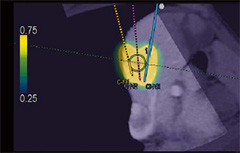

3B Sim-Navigator*

Gerçek Zamanlı Sanal Sonografi (RVS) ile hedefe yönelim süresince tekli veya çoklu iğne yollarının simülasyonunu sunmaktadır. İşaretlenen hedef ve iğne yolları arasındaki konumsal ilişki, C-düzlem ekranı ortogonalin iğne yoluna eklenmesiyle, sanal BT hacim verisinden yapılandırılan 3B vücut işareti kullanılarak gerçek zamanlı olarak değerlendirilebilir.

E-alan Simülatörü*

BT görüntüsü üzerinde birleştirilmiş renkli bir harita, RFA uygulaması süresince çoklu elektrotların verilen lokasyonundan elektrikli alanın (E-alan) dağıtımını simüle eder. Simülasyon, en uygun düzenlemenin belirlenmesi için çoklu elektrotların farklı pozisyonlarıyla yapılabilir. İğne yolunun planlanmasındaki esneklik, uygulama tekniğine belirtin gelişim taşıyabilir.